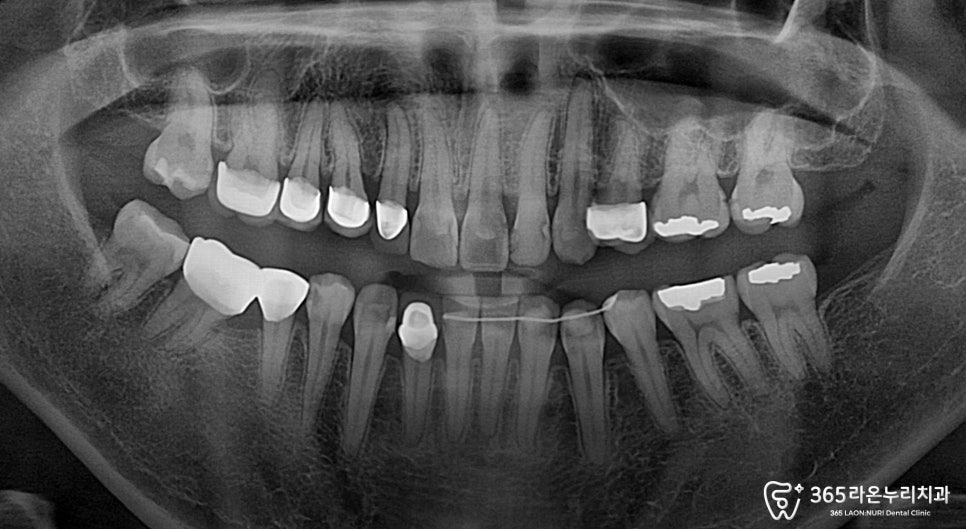

사진과 같이 앞니 쪽에도 우식증이 있고,

전체적으로 충치와 마모가 보입니다.

우선,엑스레이를 확인해 봤을 때

앞니가 충치 범위가 작고

신경이 손상되지 않은 경우, 레진 치료로

회복이 가능합니다.